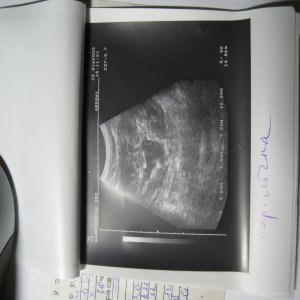

Доктор здраствуйте! мне 23 годаОколо полугода назад лежал на обследовнии в нефрологии,где был посиавлен диагноз:хр,пиелонефрит обеих почек,МКБ,микролиты обеих почек 2-4мм,наиболее крупный справа 4 мм!Было рекомендовано:курсам пить пролит,цистон,урологические сборы и тд!Все ето я принимал,почки особо не беспокоили если тока изредка небольши тупые боли в пояснице по утрам и все!Вчера решил сделать узи почек:диагноз был поставлен следующий:гидронефроз правой почки 1 степени,(врач сказал что лоханка в правой почке увеличена до 40 мм из за МКБ,лоханка левой почки 18 мм,остальные параметры в норме)микролиты обеих почек 2-4 мм,хр,пиелонефрит обеих почек!!количество мочи в течении дня нормальное,удалось сдать анализы мочи(общий и по Нечипаренко!Общий:

Чувствую себя нормально,небольшая слабость,утомляемость а так более менее!посоветуйте что нужно и можно делать в моей ситуации!какие препараты следует пропить и тд!урологов в городе нет,буду ждать ваших рекомендаций!файл с узи приложил